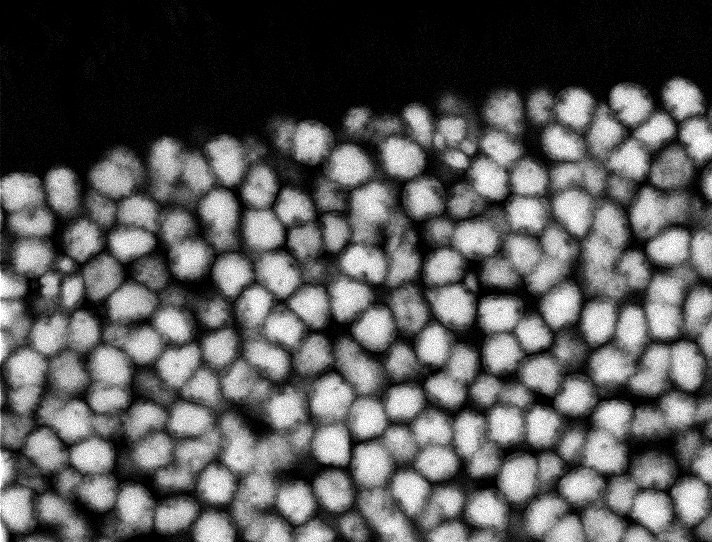

Nuclei

Nuclei - Bipolar